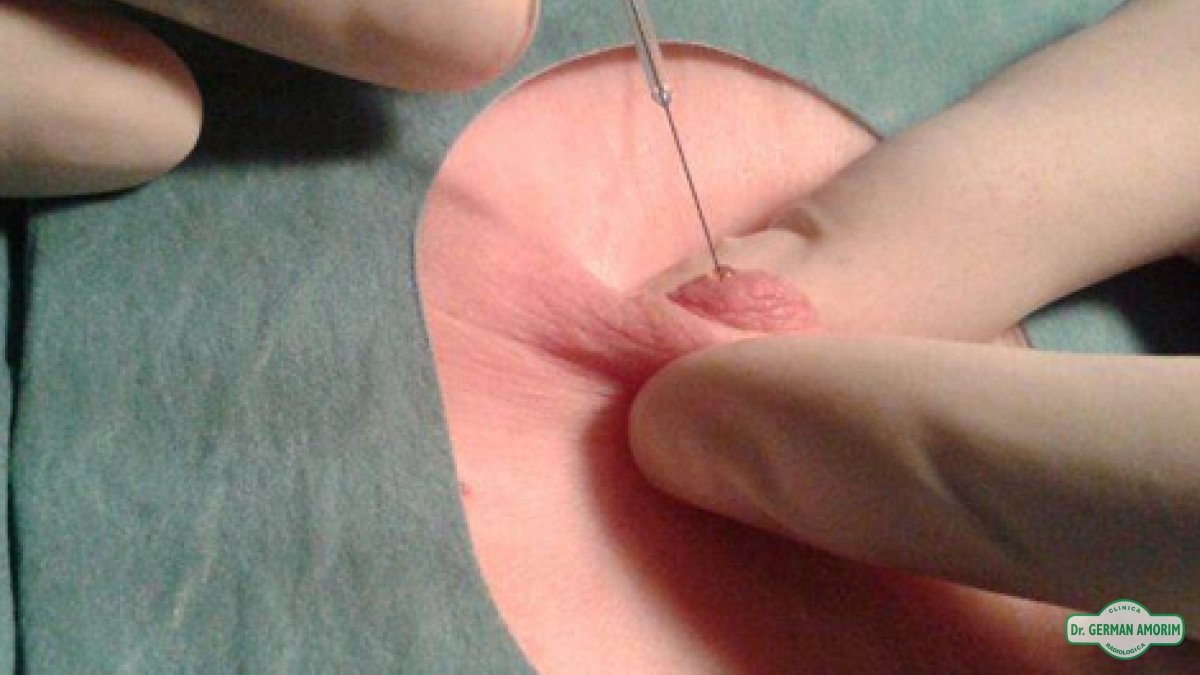

La galactografía es uno de los procedimientos intervencionistas de la mama que consiste en la realización de mamografías tras la administración de contraste radiopaco a través de un orificio en el pezón.

Como ya se había mencionado, la galactografía está indicada únicamente en los casos de secreción por el pezón de forma unilateral, uniorificial (por uno o dos orificios), espontánea y preferentemente de aspecto seroso / serosanguinolento / hemático.

Las contraindicaciones relativas son la presencia de absceso mamario, de mastitis difusa o la severa retracción del pezón, que puede hacer casi imposible la canulación de un ducto.

Tiene como mayor obstáculo la canalización del ducto en muchos casos y puede no ser concluyente en el caso de rotura del ducto canalizado.